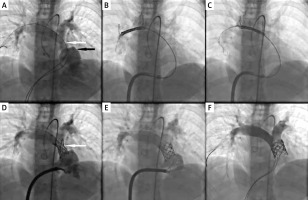

Figure 2

Step-by-step angiographic images of percutaneous pulmonary valve implantation into the narrowed first generation Xeltis Pulmonary Valve (XPV-1) conduit. A – Dilatation of proximal right ventricular outflow track (black arrow) and significant multilevel narrowing in the middle and distal part of the graft (white arrow). B – Non-expanded stent in the distal part of the right pulmonary artery branch with slightly inflated low pressure catheter balloon inside (black empty arrows). C – Stent repositioning on the slightly inflated low pressure catheter balloon (black empty arrows) to the desired position in the graft. D – Control angiography after stent implantation on the low pressure 18 mm catheter balloon in the expected position showed persistent narrowing. E – Control angiography after stent dilatation with a high pressure 20 mm catheter balloon showed total reduction of the narrowing. F – Final angiography after implantation of 22 mm valve and post-dilation with 22 mm high pressure balloon showed no pulmonary regurgitation or narrowing